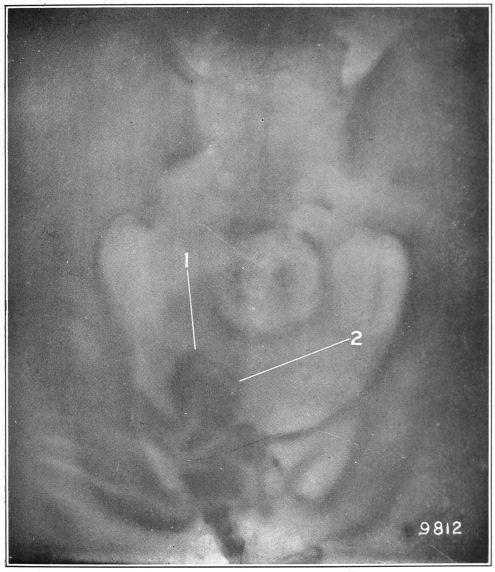

3 I found it more convenient to use the words mucus channel, mucus fistula, etc., in preference to sinus, as they better convey my ideas to the average reader.